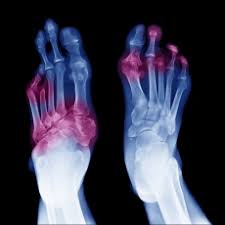

Gangraina — irish), qorason — tirik tana, aʼzo yoki toʻqimalar bir qismining irib nobud boʻlishi, nekroznnsh bir turi. Learn what role the circulatory system plays in the. Gangrene is when part of your body tissue dies. Though it usually affects your extremities, like your toes and fingers, it can also affect your internal organs. Gangrene is a type of tissue death caused by a lack of blood supply. Symptoms may include a change in skin color to red or black, numbness, swelling, pain, skin breakdown, and coolness. Gangrena — tana yoki a'zo qismlarining o'lishi (nekrozi) hisoblanib, bunda zararlangan quruq gangrenani dastlabki bosqichlarda nisbatan xavfli va og'ir bo'lgan nam shaklga o'tishini oldini olish.